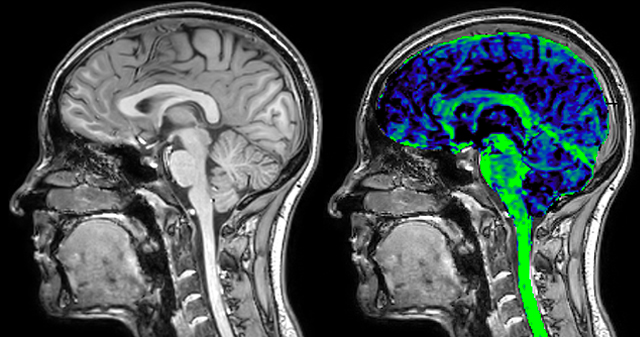

T1 - weighted

Myelin water imaging - T1 weighted

Myelin water imaging (echo 1)

Myelin water imaging with SENSE

Myelin water imaging with Compressed SENSE

With SENSE

With Compressed SENSE

Acquired resolution:

1 x 2 x 5 mm3

1.5 x 2 x 3 mm3

Number of echoes:

32 or 48

56

Echo spacing:

10 ms or 8 ms

7 ms

T1 - Weighted, Myelin Water Fraction Superimposed

MWI Spinal cord coverage

Spinal cord coverage

MWI Smaller, more isotropic voxels

Smaller, more isotropic voxels

MWI Excellent detail in quantitative maps

Excellent detail in quantitative maps

Images courtesy of Adam Dvorak, Department of Physics and Astronomy, University of British Columbia

20%

Myelin water fraction

0%